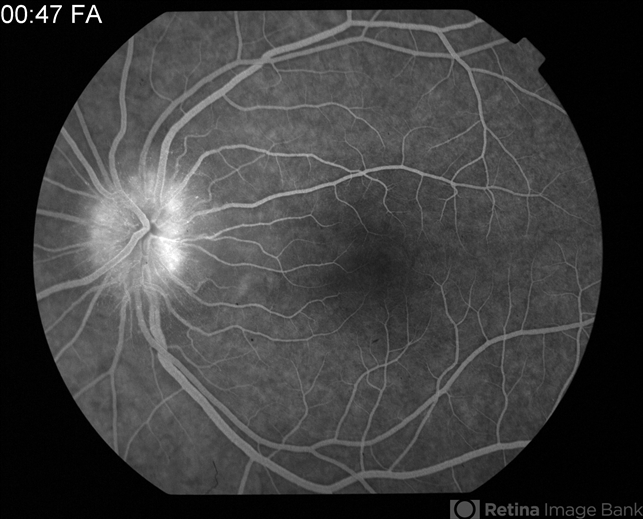

- cat scratch retinitis, Bartonella bacteria

- Tom Steele, CRA

Fundus camera

Topcon 50dx